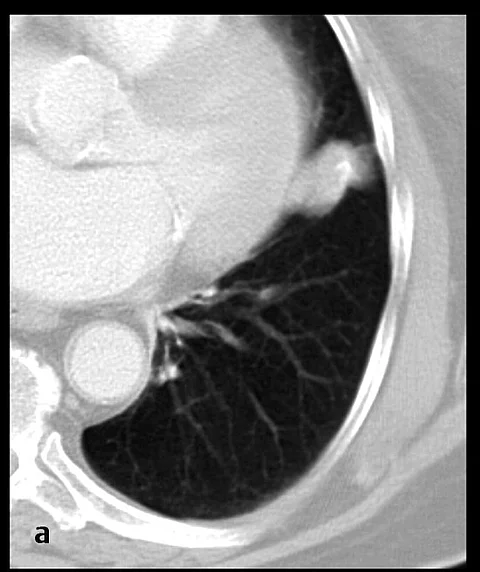

Wir haben gefragt: In dem größeren Lungenrundherd liegen Verkalkungen vor. Können diese als gutartiges Zeichen gewertet werden, so dass der Rundherd nicht weiter abgeklärt werden muss?

Sie sehen einen 2,7 × 1,5 cm großen exzentrisch verkalkten Rundherd in den kaudodorsalen Abschnitten der Lingula mit breitem Kontakt zum Lungenseptum. Ein weiterer 3 mm großer Lungenrundherd befindet sich im 9er-Segment links-subpleural.